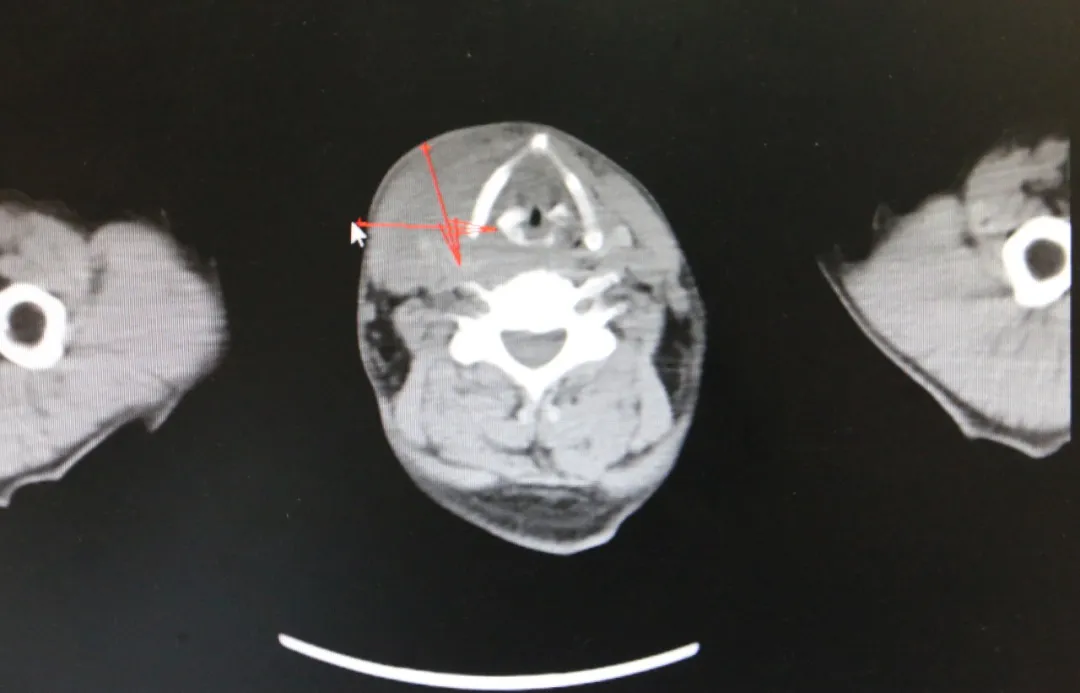

近日,济南南郊医院肿瘤科葛新华主任带领治疗团队,成功为一位50岁的下咽癌患者实施了微创介入治疗,术后患者恢复情况良好。

这位患者曾辗转北京与青岛的多家三甲医院,但治疗效果并不理想。在绝望之际,他了解到济南南郊医院肿瘤科葛新华主任的治疗团队,于是抱着最后的希望来到该院就医。经过葛新华主任团队的细致检查与评估,为患者量身定制了微创介入治疗的手术方案。

DSA微创介入灌注栓塞术,是一种在不开刀暴露病灶的情况下,通过微小通道或人体原有管道,在DSA影像设备的引导下,对病灶进行精准定位与治疗的先进技术。该技术通过微创穿刺股动脉进入血管系统,精准插入肿瘤病灶,注射血管栓塞剂对肿瘤病灶周围血管进行栓塞,从而切断肿瘤细胞的营养供应通道,使其无法增长与转移。同时,通过导管注入高浓度的化疗药物,对肿瘤组织进行破坏,直至将其“饿死”消亡。整个治疗过程安全、高效,患者术后可安返病房,正常生活饮食不会受到任何影响。